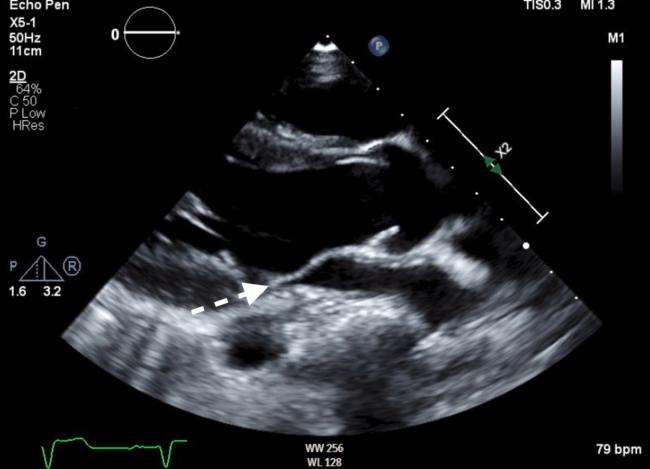

Unileaflet Mitral Valve in Patient With Marfanoid Habitus.

• Unileaflet mitral valve is a very rare congenital heart condition. • It is usually lethal in neonates with severe regurgitation. • Rare asymptomatic cases can be diagnosed later in life.